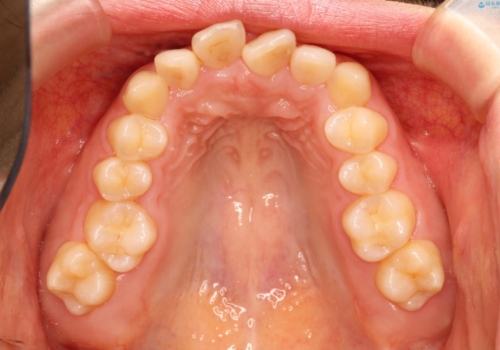

初診時の歯並びの状態としては、上下とも前歯部の中等度のがたつきがあり、その他に奥歯の噛み合わせのズレや、口元の突出感も認められました。

抜歯矯正の可能性もご提案しましたが、ご本人の強い希望もあり、抜歯なし/インビザラインによるマウスピース矯正にて治療を行いました。

本症例は、見た目、嚙み合わせ及び、治療期間や施術内容にご満足いただきました。